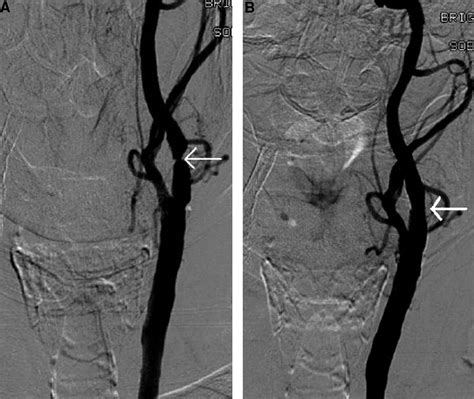

• Cerebral Angiography: An invasive procedure where a catheter is threaded to the neck to provide the most precise view of the blockage.